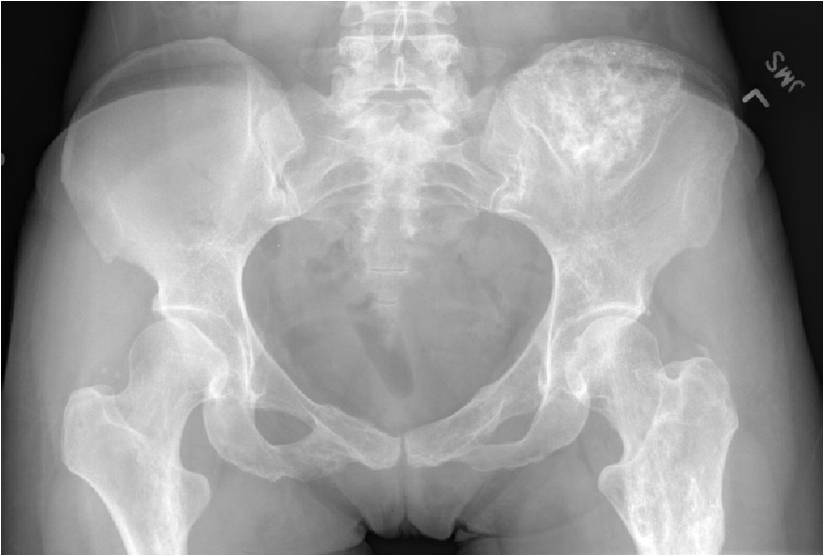

- Enchondromas of the pelvis, vertebrae and ribs are uncommon

- Almost all hyaline cartilage tumors of the pelvis are considered malignant based on anatomic location no matter what the pathology shows. These tumors will ultimately grow locally and have the potential to dedifferentiate or change into a higher grade chondrosarcoma.

Metaphyseal Tumor Heavy Calcifications Ring and Arc Pattern of Calcifications Minimal Endosteal Scalloping No Cortical Destruction No Periosteal Reaction No Cortical Destruction No Soft Tissue Component